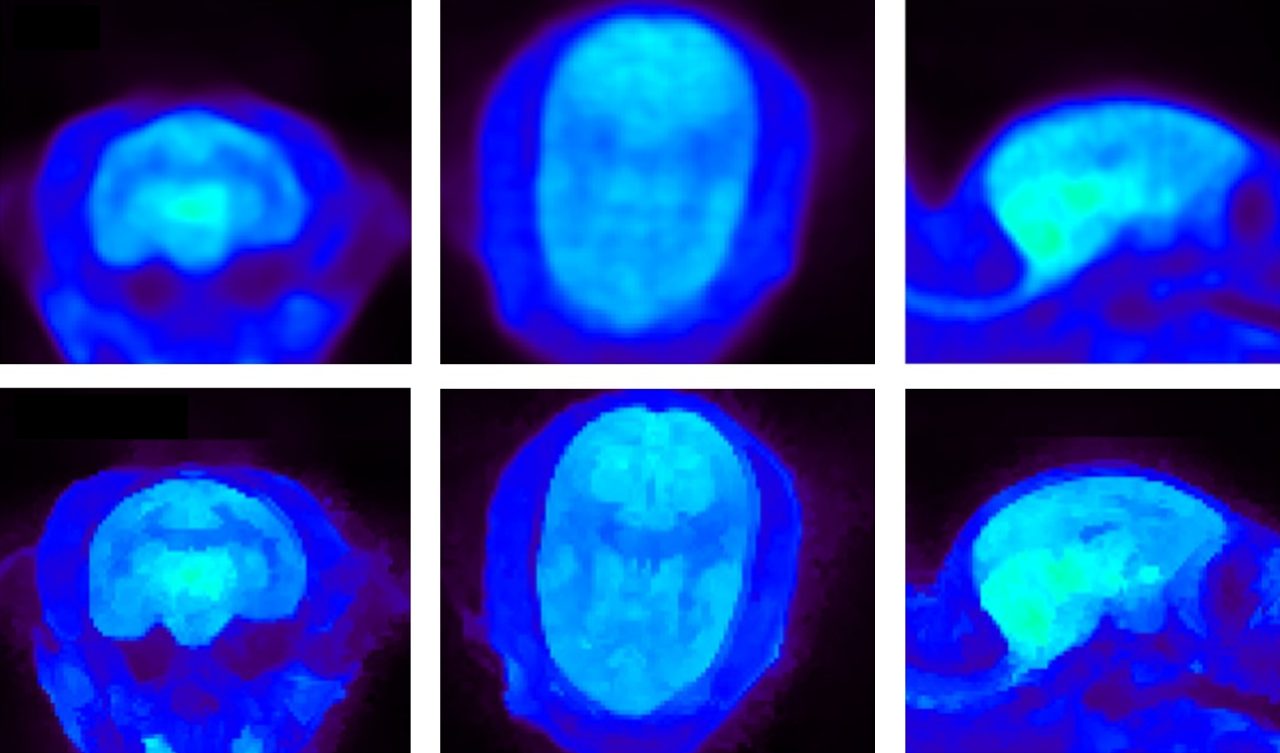

使用PET FDG对狨猴进行脑部成像。上图:MAP重建。下图:Bowsher Prior重建,一种先进的PET重建算法。图片来源:S. Valable与M Naveau,法国卡昂Cyceron研究所。